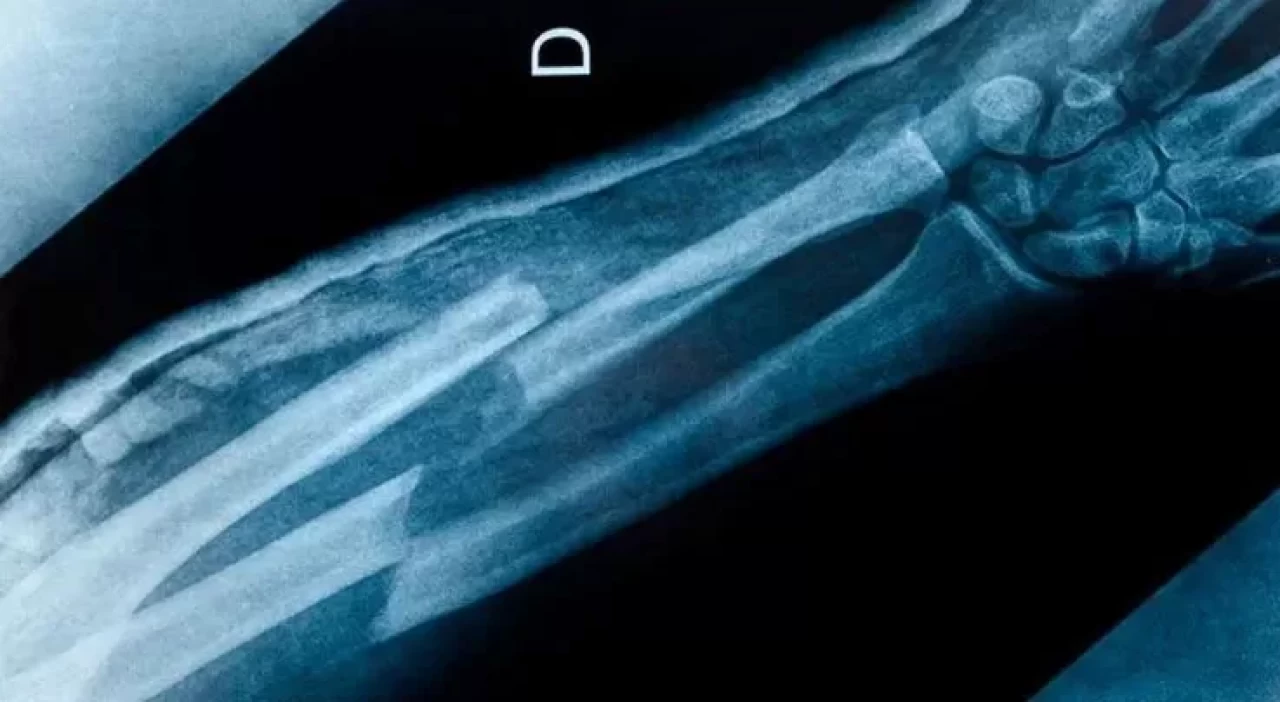

Sosyal medyada "hiç kemiği kırılmamış kişiler" hakkında üç sıra dışı teori öne atıldı. Ancak bilim insanları iddiaların tam tersini söylüyor.

Hayatı boyunca hiç kemiğini kırmayan insanlar zaman zaman bu durumu bir “şans” olarak değerlendirir.